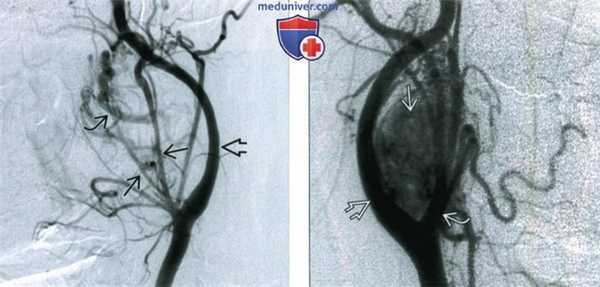

(Слева) Ангиография общей сонной артерии, боковая проекция. В артериальную фазу визуализируются крупные питающие сосуды. Также имеется артериовенозный сброс, который приводит к раннему появлению на изображении одной из увеличенных вен. Внутренняя сонная артерия смещена кзади.

(Справа) Ангиография общей сонной артерии, боковая проекция, поздняя артериальная фаза. Между наружной и внутренней сонными артериями определяется каротидная параганглиома.